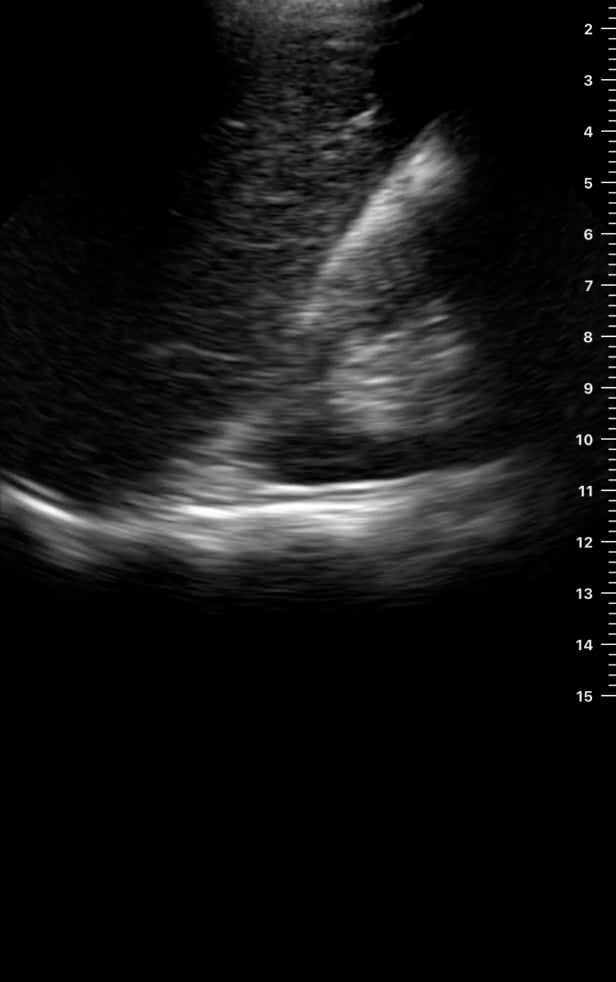

Ascites refers to the abnormal accumulation of fluid within the peritoneal cavity, the space surrounding abdominal organs. In medical imaging, particularly with ultrasound, ascites presents as an anechoic (black) or hypoechoic (dark) fluid collection, often outlining bowel loops or organs. This condition is a key indicator of underlying pathologies such as liver cirrhosis, heart failure, kidney disease, or certain cancers, requiring accurate diagnosis for proper patient management.

Ultrasound is a crucial tool for detecting and quantifying abdominal ascites due to its real-time imaging capabilities and portability. Sonographers can effectively visualize even small amounts of fluid, aiding in diagnostic assessments and guiding therapeutic procedures like paracentesis. Understanding ascites on ultrasound is essential for precise medical diagnosis and optimizing patient care in abdominal evaluations.